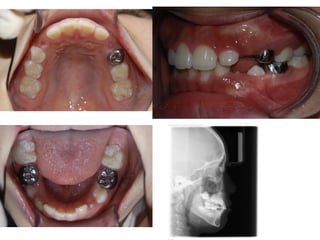

S.H. Jang

1999.10.14/M

C.C

• Max. protrusion

• Lower crowding

Dx

• Mouth breathing, retro-positioned tongue

Goal

• Lip seal(Adenoidectomy and Tonsilectomy)

• Establish tongue posture with T4K

2006.07.21

A &T 2008.01 Tr start

2007.11.21

2008.05.08 4m